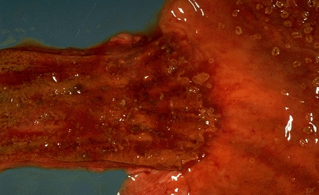

(1)肉眼观,食管下段粘膜出现长短不等、条状发红的糜烂面。

(2)镜下见粘膜充血、水肿和嗜中性粒细胞和嗜酸性粒细胞浸润,继而粘膜糜烂、脱落,累及粘膜下层常出现溃疡。相邻鳞状上皮的基底细胞增生,上皮脚下延和固有膜乳头上伸。长期胃液返流刺激,病变经久不愈,由于肉芽组织增生,纤维化及至瘢痕形成,可导致食管缩短、变形和狭窄。